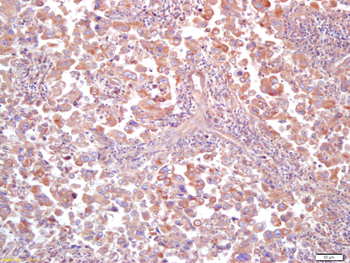

IF, IHC-Fr, IHC-P, WB

应用稀释比例:WB=1:500-2000, IHC-P=1:100-500, IHC-F=1:100-500, IF=1:100-500